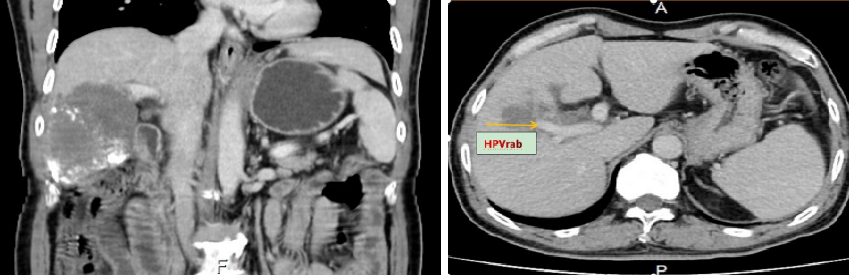

系统治疗6周期后影像复查:

上腹部CT增强扫描2021-11-29诊断意见:1、肝癌并肝内多发转移治疗后改变,病灶较前缩小,其内见多发碘油沉积。建议定期复查。

上腹部MRI增强(普美显)2021-11-29诊断意见:1、肝右叶肝细胞肝癌并肝右叶多发转移治疗后改变,肝周少量积液。2、胆囊炎征象。

疗效评价:PR RECIST标准(实体瘤)及肿瘤化疗疗效评价标准。